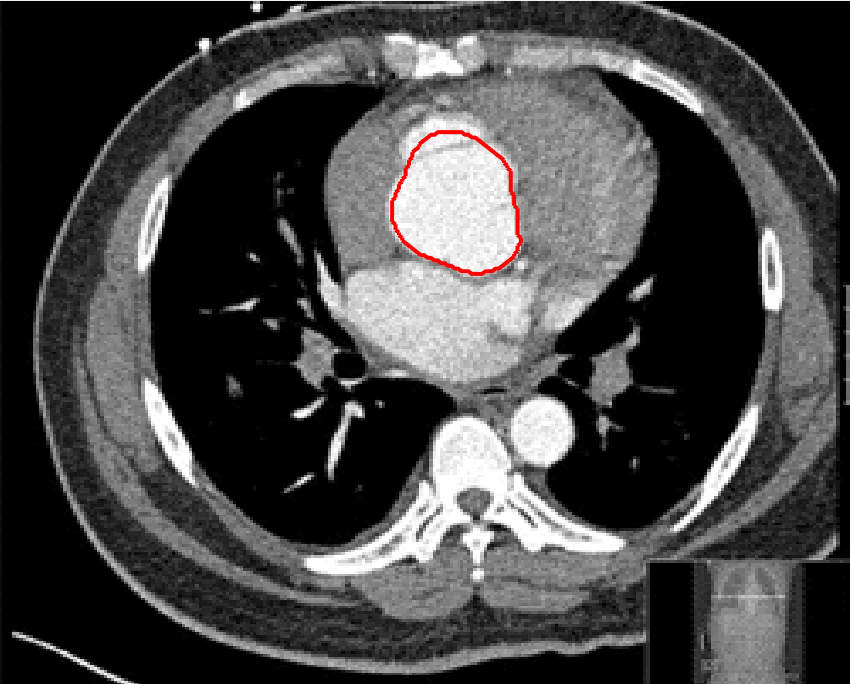

Four sets of test results are shown below. In Test 1 we compare models M1 – M6 to the proposed model M7 for two images which are hard to segment. The first is a CT scan from which we would like to segment the lower portion of the heart, the second is an MRI scan of a knee and we would like to segment the top of the Tibia. See Figure 9 for the test images and the marker sets used in the experiments. In Test 2 we will review the sensitivity of the proposed model to the main parameters. In Test 3 we will give several results achieved by the model using marker and anti-marker sets. In Test 4 we show the initialisation independence and marker independence of the Geodesic Model on real images.

In this test we give the segmentation results for models M1 – M7 for the two challenging test images shown in Figure 9. The marker and anti-marker sets used in the experiments are also shown in this figure. After extensive parameter tuning, the best final segmentation results for each of the models are shown in Figures 10 and 11. For M1 – M4 we obtain incorrect segmentations in both cases. In particular, the results of M2 and M4 are interesting as the former gives poor results for both images, and the latter gives a reasonable result for Test Image 1 and a poor result for Test Image 2. In the case of M2, the regularisation term includes the edge detector and the distance penalty term (see (4)). It is precisely this which permits the poor result in Figures 10(b) and 11(b) as the edge detector is zero along the contour and the fitting terms are satisfied there (both intensity and area constraints) – the distance term is not large enough to counteract the effect of these. In the case of M4, the distance term and edge detector are separated from the regulariser and are used to weight the Chan-Vese fitting terms (see (9)). The poor segmentation in Figure 11(b) is due to the Chan-Vese terms encouraging segmentation of bright objects (in this case), weighting enforces these terms at all edges in the image and near . In experiments, we find that M4 performs well when the object to segment is of approximately the highest or lowest intensity in the image, however when this is not the case, results tend to be poor. We see that, in both cases, models M5 and M6 give much improved results to M2 and M4 (obtained by incorporating the geodesic distance penalty into each). The proposed Geodesic Model M7 gives an accurate segmentation in both cases. It remains to compare M5, M6 and M7. We see that M5 is a non-convex model (and cannot be made convex [39]), therefore results are initialisation dependent. It also requires one more parameter than M6 and M7, and an accurate set to give a reasonable area constraint in (4). These limitations lead us to conclude M6 and M7 are better choices than M5. In the case of M6, it has the same number of parameters as M7 and gives good results. M6 can be viewed as the model M7 with weighted intensity fitting terms (compare (18) and (30)). Experimentally, we find that the same quality of segmentation result can be achieved with both models generally, however M6 is more parameter sensitive than M7. This can be seen in the parameter map in Figure 12 with M7 giving an accurate result for a wider range of parameters than M6. To show the improvement of M7 over previous models, we also give an image in Figure 13 which can be accurately segmented with M7 but the correct result is never achieved with M6 (or M3). Therefore we find that M7 outperforms all other models tested M1 – M6.